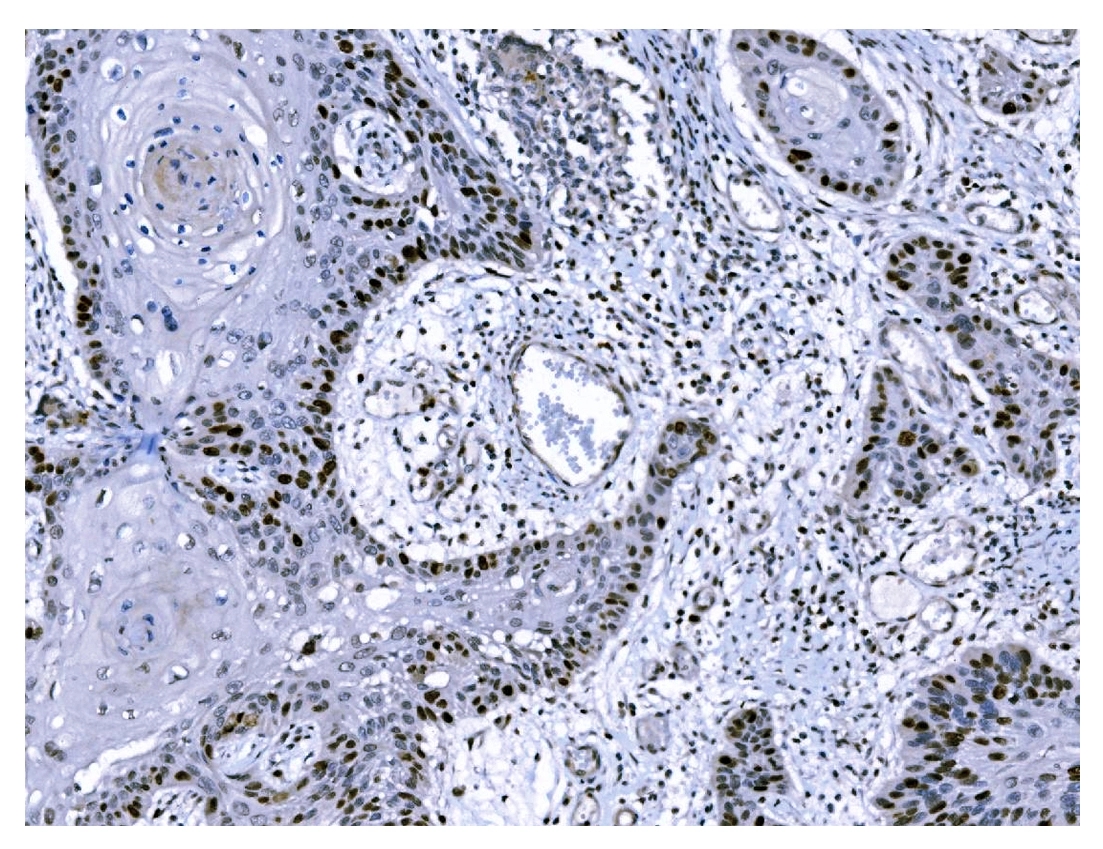

IHC analysis of Ki67/MKI67 using anti-Ki67/MKI67 antibody (M00254-9).

Ki67/MKI67 was detected in a paraffin-embedded section of human lung cancer tissue. Biotinylated goat anti-mouse IgG was used as secondary antibody. The tissue section was incubated with mouse anti-Ki67/MKI67 Antibody (M00254-9) at a dilution of 1:200 and developed using Strepavidin-Biotin-Complex (SABC) (Catalog # SA1021) with DAB (Catalog # AR1027) as the chromogen.